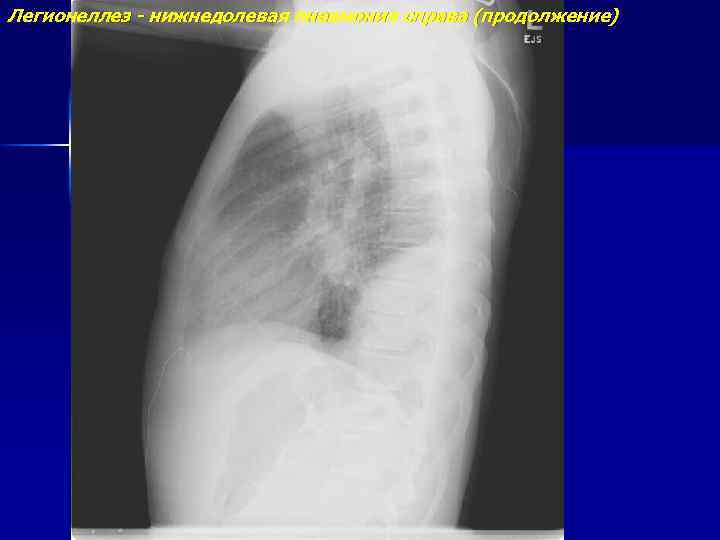

Легионеллез - нижнедолевая пневмония справа

Легионеллез - нижнедолевая пневмония справа (продолжение)